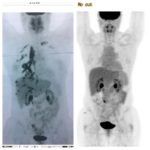

I decided to go on a pre-planned vacation to Peru the following week and hiked Machu Picchu. I was sure that my lungs were just fine since I had no symptoms. Upon returning my oncologist ordered a PET scan. The day of the scan has become the hardest day of my life. . . thus far. The scan came back showing metastasis throughout my left lung, sternum, and right neck lymph nodes. A biopsy 2 weeks later confirmed the cancer was back and had mutated to a much more aggressive form of breast cancer (triple positive).

December 2018- After returning home from Hope 4 Cancer and receiving 4 treatments at the Mayo clinic in the previous 3 months, I had my first repeat PET Scan to check for progress. My daughter was in town to spend December with me all the way from Sweden knowing we may have limited time together. On December 14, 2018 I had the scan and we were together to get the results. After only 3 months and a month at Hope 4 Cancer my scan was completely clean!!! NO EVIDENCE OF DISEASE IN MY BODY!